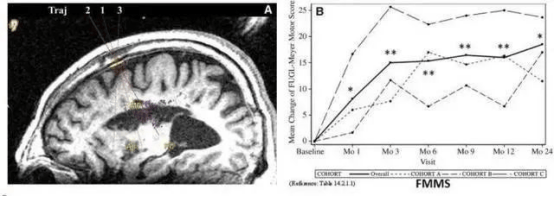

2019年我国解放军总医院发表于《干细胞转化医学》研究显示,神经干细胞回输有助于脑卒中偏瘫患者运动功能恢复。

9名偏瘫患者接受人源神经干细胞脑内回输后,影像学显示植入区出现新的神经组织,证明其有一定临床益处。

△9例患者的影像学显示病变区域的组织发生明显变化